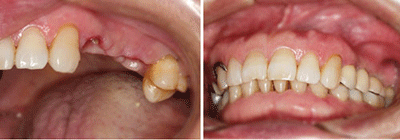

想要具体了解牙齿烂了咋办?能补好吗 点击【在线咨询】直接问医生!方便!快捷!经过调查发现,百分之九十九的人都患者蛀牙,每个人的蛀牙程度都不同,这是对我们的自身健康是个极大的危害。而烂牙就是因为蛀牙而产生的牙洞,如果没有及时处理,牙齿将会失去鲜亮的外形,成为残根残冠。除了蛀牙之外,有些患者也可能会因为疾病放射治疗后牙齿变脆弱,不小心吃到硬物导致牙齿折断,而且因为外力撞击也可能导致牙齿折断,也就是俗称的烂牙。

但是不管怎样,烂牙是需要我们及时拔除的,否则会造成更加严重的后果,但是烂牙拔掉之后不补也会给我们的生活造成很严重的影响,比如缺牙了,说话会漏风,咀嚼功能和效率就会受到影响,并会进一步影响消化系统的功能,而它对我们的发音、外观都有一定的影响,所以补牙是很有必要的,如今兴起的种植牙术就是个不错的补牙方式。直接与医院在线医师一对一通话,方便!快捷!了解详情就医指导。

医生指出,常见的修复缺失牙的方法有三种,即活动义齿、固定义齿、种植义齿,它们各有所长。

3.种植义齿,老百姓称之为“种植牙”,其原理是在缺失牙的部位将纯钛的种植体植入牙床内。3个月后,种植体通过表面的生物活性涂层与周围骨质发生骨融合,然后在种植体上安装牙冠或牙桥,其结构与感觉类似于天然牙齿,无需取戴,咀嚼功能强,既克服了活动义齿的不美观、不舒适、每天需清洗的缺点,又不需要磨削缺牙部位相邻的健康牙。目前这种镶牙法,成为口腔医学界公认的缺失牙的修复方法。